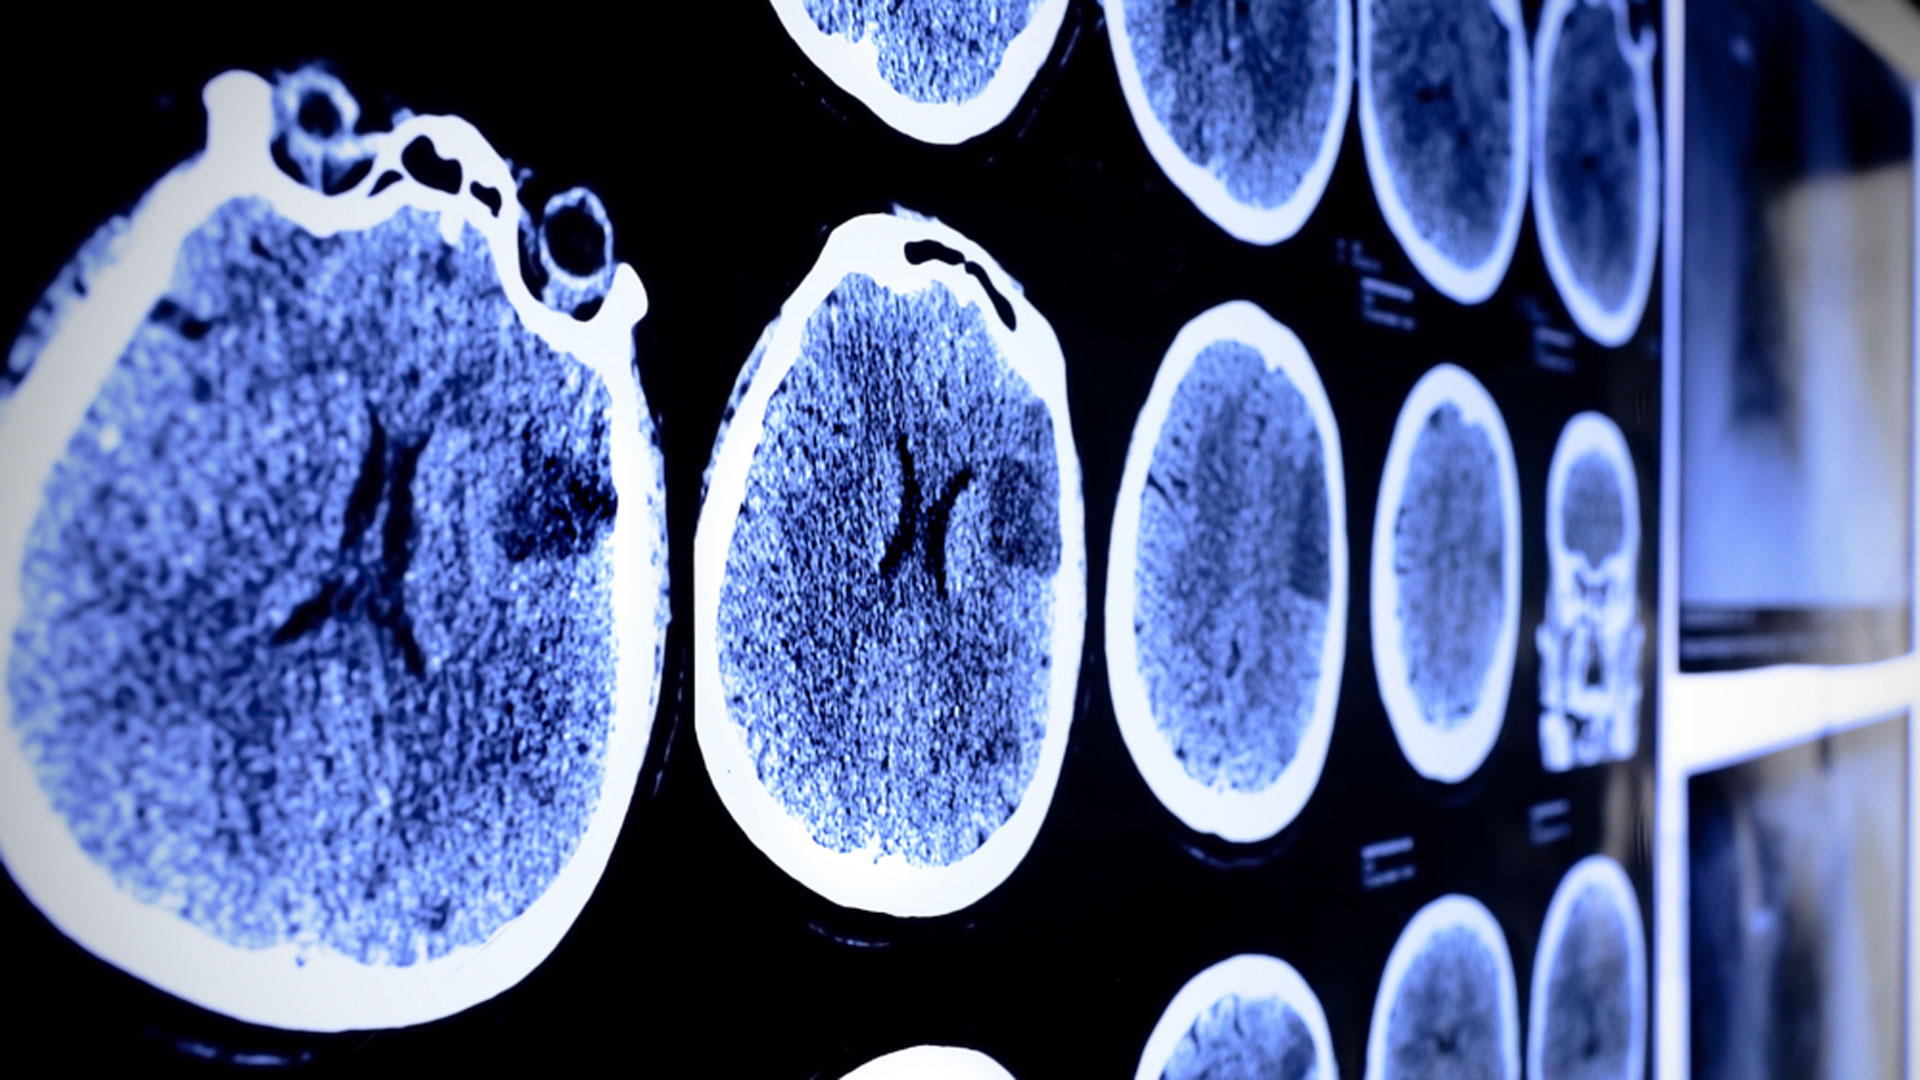

Se busca contar con biomarcadores que permitan acceder a un diagnóstico precoz para aumentar las posibilidades de frenar la enfermedad con fármacos/Archivo

Se busca contar con biomarcadores que permitan acceder a un diagnóstico precoz para aumentar las posibilidades de frenar la enfermedad con fármacos/ArchivoEl trastorno implica una degeneración irreversible del cerebro. Provoca alteraciones de la memoria, la cognición, la personalidad y otras funciones que, a la larga, pueden conducir a la muerte por fallo cerebral completo.

Las personas con padres que tiene Alzheimer causado por una mutación tienen un riesgo del 50% de desarrollar la enfermedad/Archivo

Las personas con padres que tiene Alzheimer causado por una mutación tienen un riesgo del 50% de desarrollar la enfermedad/ArchivoSe sabe que las personas con un progenitor con Alzheimer causado por una mutación tienen un riesgo del 50% de desarrollar la enfermedad. Para el nuevo estudio, los investigadores analizaron 164 muestras de plasma sanguíneo de 33 portadores de la mutación y 42 familiares sin la predisposición patogénica heredada. Los datos se recolectaron entre los años 1994 y 2018.

El primer cambio del aumento de la proteína GFAP se puede detectar diez años antes de los primeros síntomas de la enfermedad/Archivo

El primer cambio del aumento de la proteína GFAP se puede detectar diez años antes de los primeros síntomas de la enfermedad/ArchivoEl estudio se financió con subvenciones de varios organismos, entre ellos la Fundación Sueca del Cerebro, la Fundación Sueca del Alzheimer y con subvenciones para proyectos de la ALF (véase la lista completa en el estudio). Los autores, Kaj Blennow y Henrik Zetterberg, participan en varias colaboraciones con empresas farmacéuticas privadas.